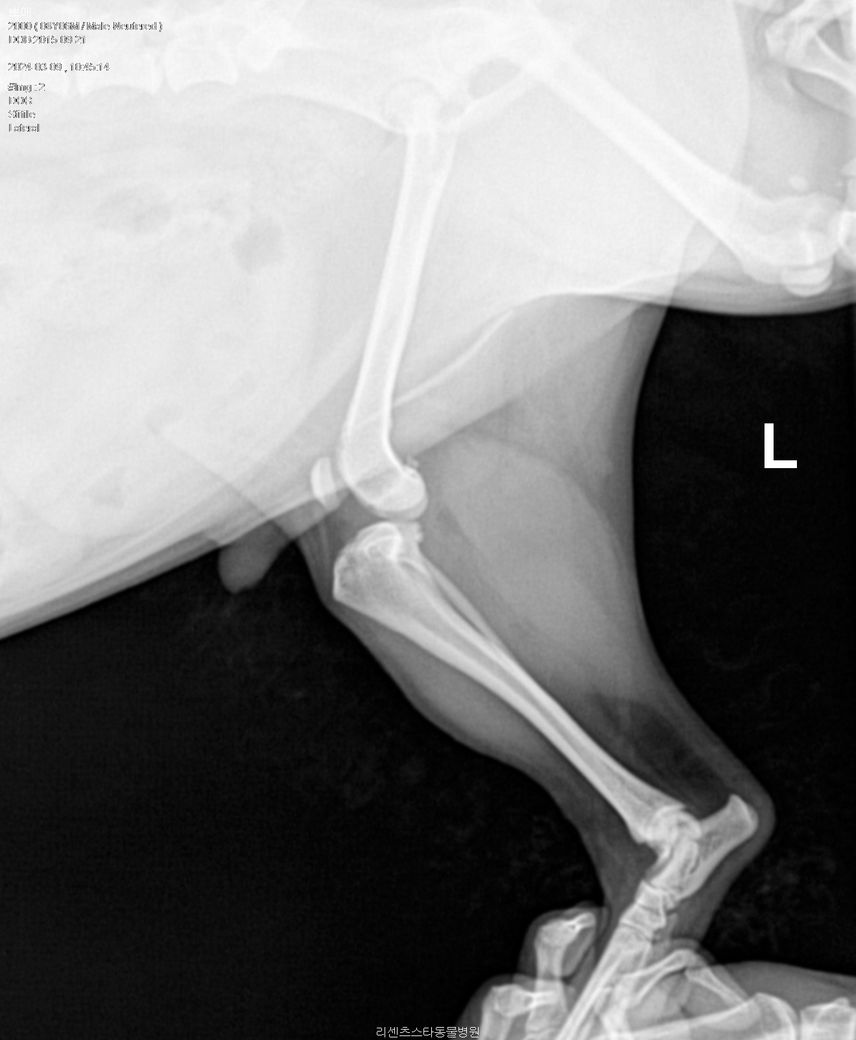

아픈 쪽 다리는 왼쪽 뒷 다리(L) 사진입니다

방사선 촬영만으로는 십자인대 단열을 확진할 수는 없겠지만 지금 왼쪽 다리를 보시면 아예 정강 뼈가 전방으로 변위가 심한 것을 보면 십자인대 완전 단열을 가능성이 매우 큽니다.

경골이 전방변위 되어 있으며 관절낭이 심하게 종창되어 있습니다. 전형적인 십자인대 단열 혹은 부분단열 소견으로 주치의의 판단이 옳으니 의심하지 말고 주치의의 의견을 따르시기 바랍니다.